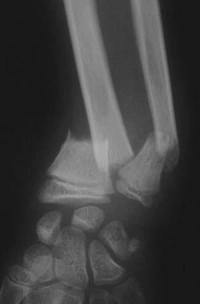

Métaphyse poignet -1 Radio post-opératoire Face

Radio post-opératoire après embrochage intrafocal du radius et centro-médullaire de l'ulna